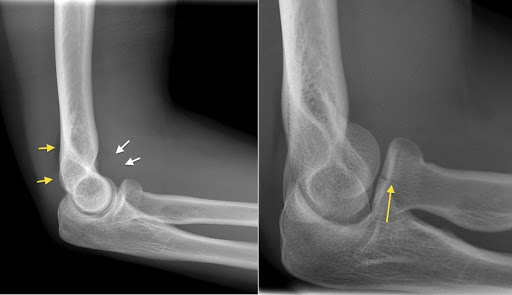

They did get the x ray images, but their system for sharing it with the radiologist was down. You can see the break/crack in the image, but there was no one on staff to officially diagnose it. So I at least got the images taken and confirmation it is indeed broken. Gotta wait for a radiologist or doctor to look at the x rays and tell me how bad. There isn't a ton of swelling so I got my fingers crossed it's not bad and everything is more or less in place.

That sounds like a radial head fracture. This should heal fine, as the intact ulnar stabilizes it.

I agree with TLS sounds like a radial head fx. I'll try to find an image an post it. Tell me if it looks like yours. (I read a ton of films for urgent care and most of the PAs and especially NPs have no idea how to order x rays properly let alone examine a joint or know the treatment).